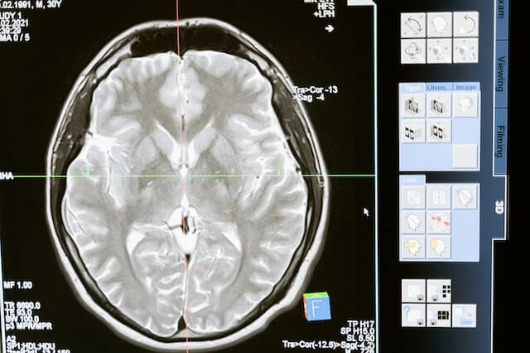

뇌졸증이 발생한 후, 적절한 치료와 회복 과정을 거쳐 건강을 되찾아가는 것이 중요합니다. 전문가 인터뷰와 생생한 케이스 스터디를 통해 뇌졸증 치료 및 회복 과정에 대한 인식을 높이고 이 글을 읽는 분들에게 도움이 되는 정보를 제공합니다. 뇌졸증 치료의 핵심은 최대한 빠른 시간 내에 손상된 뇌 영역의 기능을 회복하는 것입니다. 전문가 인터뷰를 통해 알게 된 대표적인 치료 방법은 다음과 같습니다. 첫째, 허혈성 뇌졸중의 경우 뇌 혈류를 회복시키는 데 초점을 맞추어 혈전 용해제를 사용합니다. 이 방법은 빠른 시간 내에 적용될수록 더 효과적입니다. 둘째, 출혈성 뇌졸중은 혈압 관리와 출혈 부위의 수술적 대응이 필요하며, 경우에 따라 뇌압을 낮추기 위한 치료가 진행될 수 있습니다. 회복 과정에서는 적절한 재활 치료가 필수적입니다. 생생한 케이스 스터디를 통해 뇌졸중 환자들이 겪는 회복 과정을 알아보았습니다. 첫째, 이동과 일상생활 지원을 위한 물리치료를 받으며 꾸준한 운동으로 근력을 회복합니다. 둘째, 언어 및 인지 기능을 개선하기 위한 언어 치료를 진행하며, 소통 능력을 차츰 회복해 갑니다. 셋째, 교통사고 예방 교육과 새로운 적응 기술을 배우는 직업 치료를 통해 일상생활을 독립적으로 수행할 수 있도록 지원합니다. 뇌졸중 치료 및 회복 과정에 대한 이해와 소통은 환자와 가족 모두에게 도움이 됩니다. 이를 통해 뇌졸중 환자들이 더 나은 삶을 살아가는 길을 찾을 수 있다는 것을 기억하시기 바랍니다.